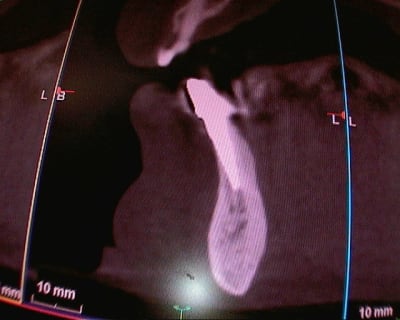

> Voici le cas en image

> Mon doute portait donc sur la face vestibulaire de l'implant en place de 43.

> Implant4.5*11 Astra

> Excusez moi pour la pano avec le stellite.

Rappelons qu'en mesurant j'ai 1.25 mm d'os au final et pas 0.5-0.8mm